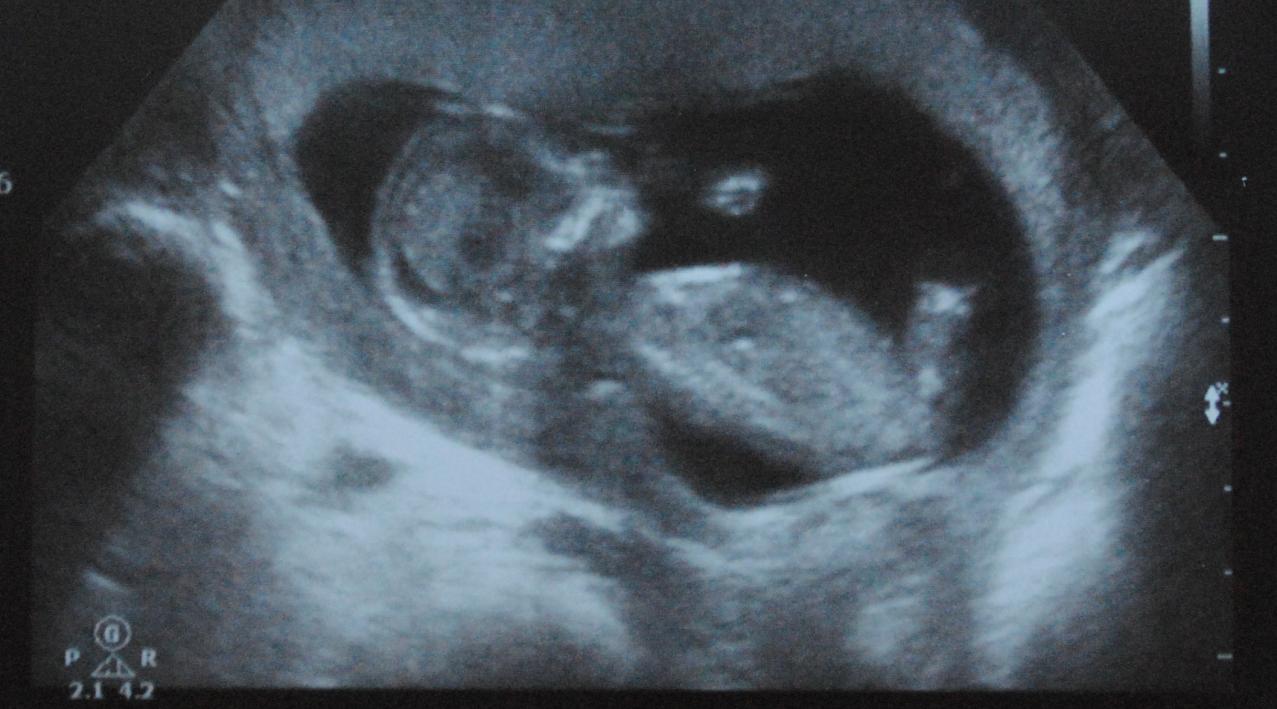

Attachment 85

Is this picture any better?

Cheers!

boy? maybe..lol..hard one to guess on! Can't wait for an update!!

mayb Boy!

Thats atricky one, I think the main of the nub is hidden behind the leg, do you have any other pictures at all??